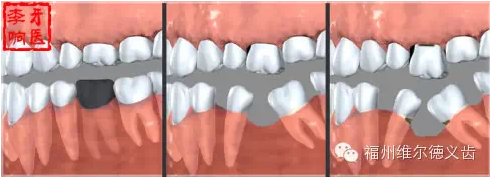

好,這次又沒得到妥善處理,接下來牙體組織隨著齲壞進展崩解嚴(yán)重,只能拔了,這步不貴,拔牙通常很便宜,一般難度的兩三百元足夠了,但是接下來是后續(xù)的問題:拔牙之后需要鑲,鑲牙就有很多方式了,目前比較好的鑲牙方式種植牙,一般要上萬元,這個價格我也覺得很貴,但沒辦法,誰讓老天賜給的牙被揮霍壞了呢,能有人工補救的機會已經(jīng)要感謝醫(yī)療科技的進步了,有些人想種牙還受身體條件限制種不了呢。

QQ圖片20150725100230.png

你說種牙太貴我不鑲了,我挺著,時間久了,兩邊的牙向缺牙的地方倒了,對應(yīng)的咬合面上的牙齒伸長了,這時候會發(fā)現(xiàn)缺牙附近前后左右的牙吃東西都塞牙,長期的塞牙造成其他牙齒的齲壞,開始了上述的循環(huán),這時候的治療費用不是一顆牙的問題,要乘上壞牙的數(shù)量,更貴了。什么?你深感缺牙不便,又想鑲了?有些可以先正畸恢復(fù)到剛?cè)毖罆r候的狀態(tài),再鑲,當(dāng)然,正畸又有一筆費用。有些沒有辦法鑲了,想花錢也花不出去了。

QQ圖片20150725100245.png